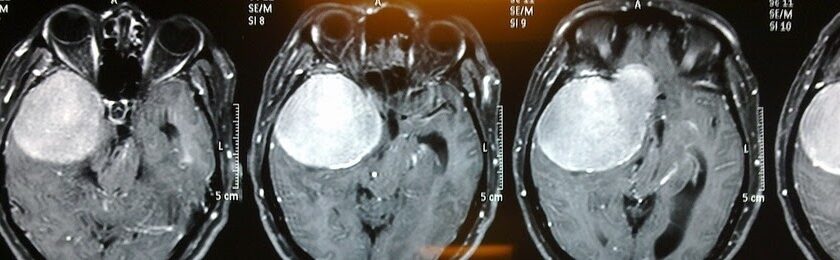

Видалення менінгіоми — серйозне випробування для організму. Операція на головному мозку завжди пов’язана з ризиками і потребує тривалого відновлення. Пацієнт може зіткнутися з різними труднощами: від слабкості й запаморочення до порушення рухів чи мовлення. Щоб повернути працездатність і звичне життя, важливо знати, як правильно відновлюватися після операції, які етапи реабілітації існують і які обмеження варто враховувати. Детальніше про можливі наслідки можна дізнатися за посиланням https://time.org.ua/naslidky-pislya-vydalennya-meningiomy/, де розглянуто типові ускладнення та рекомендації після втручання.

Після видалення менінгіоми головного мозку пацієнт зазвичай перебуває у стаціонарі від кількох днів до кількох тижнів, залежно від складності операції. У цей період лікарі стежать за станом свідомості, координацією рухів, роботою нервової системи.